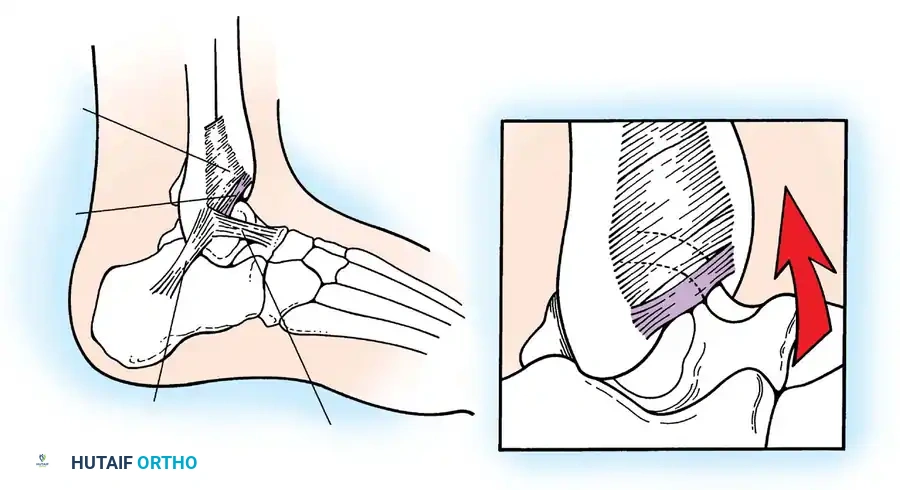

Soft-Tissue Impingement (Bassett’s Ligament)

Soft-tissue impingement often occurs anterolaterally following an inversion sprain. Bassett et al. identified that a thickened distal fascicle of the anterior inferior tibiofibular ligament (AITFL) can impinge on the anterolateral aspect of the talus during dorsiflexion, causing localized chondromalacia and chronic pain.

Fig. 8: Lateral aspect of the ankle joint demonstrating the distal fascicle of the AITFL (Bassett's ligament). With dorsiflexion, this thickened fascicle impinges on the anterolateral talus.